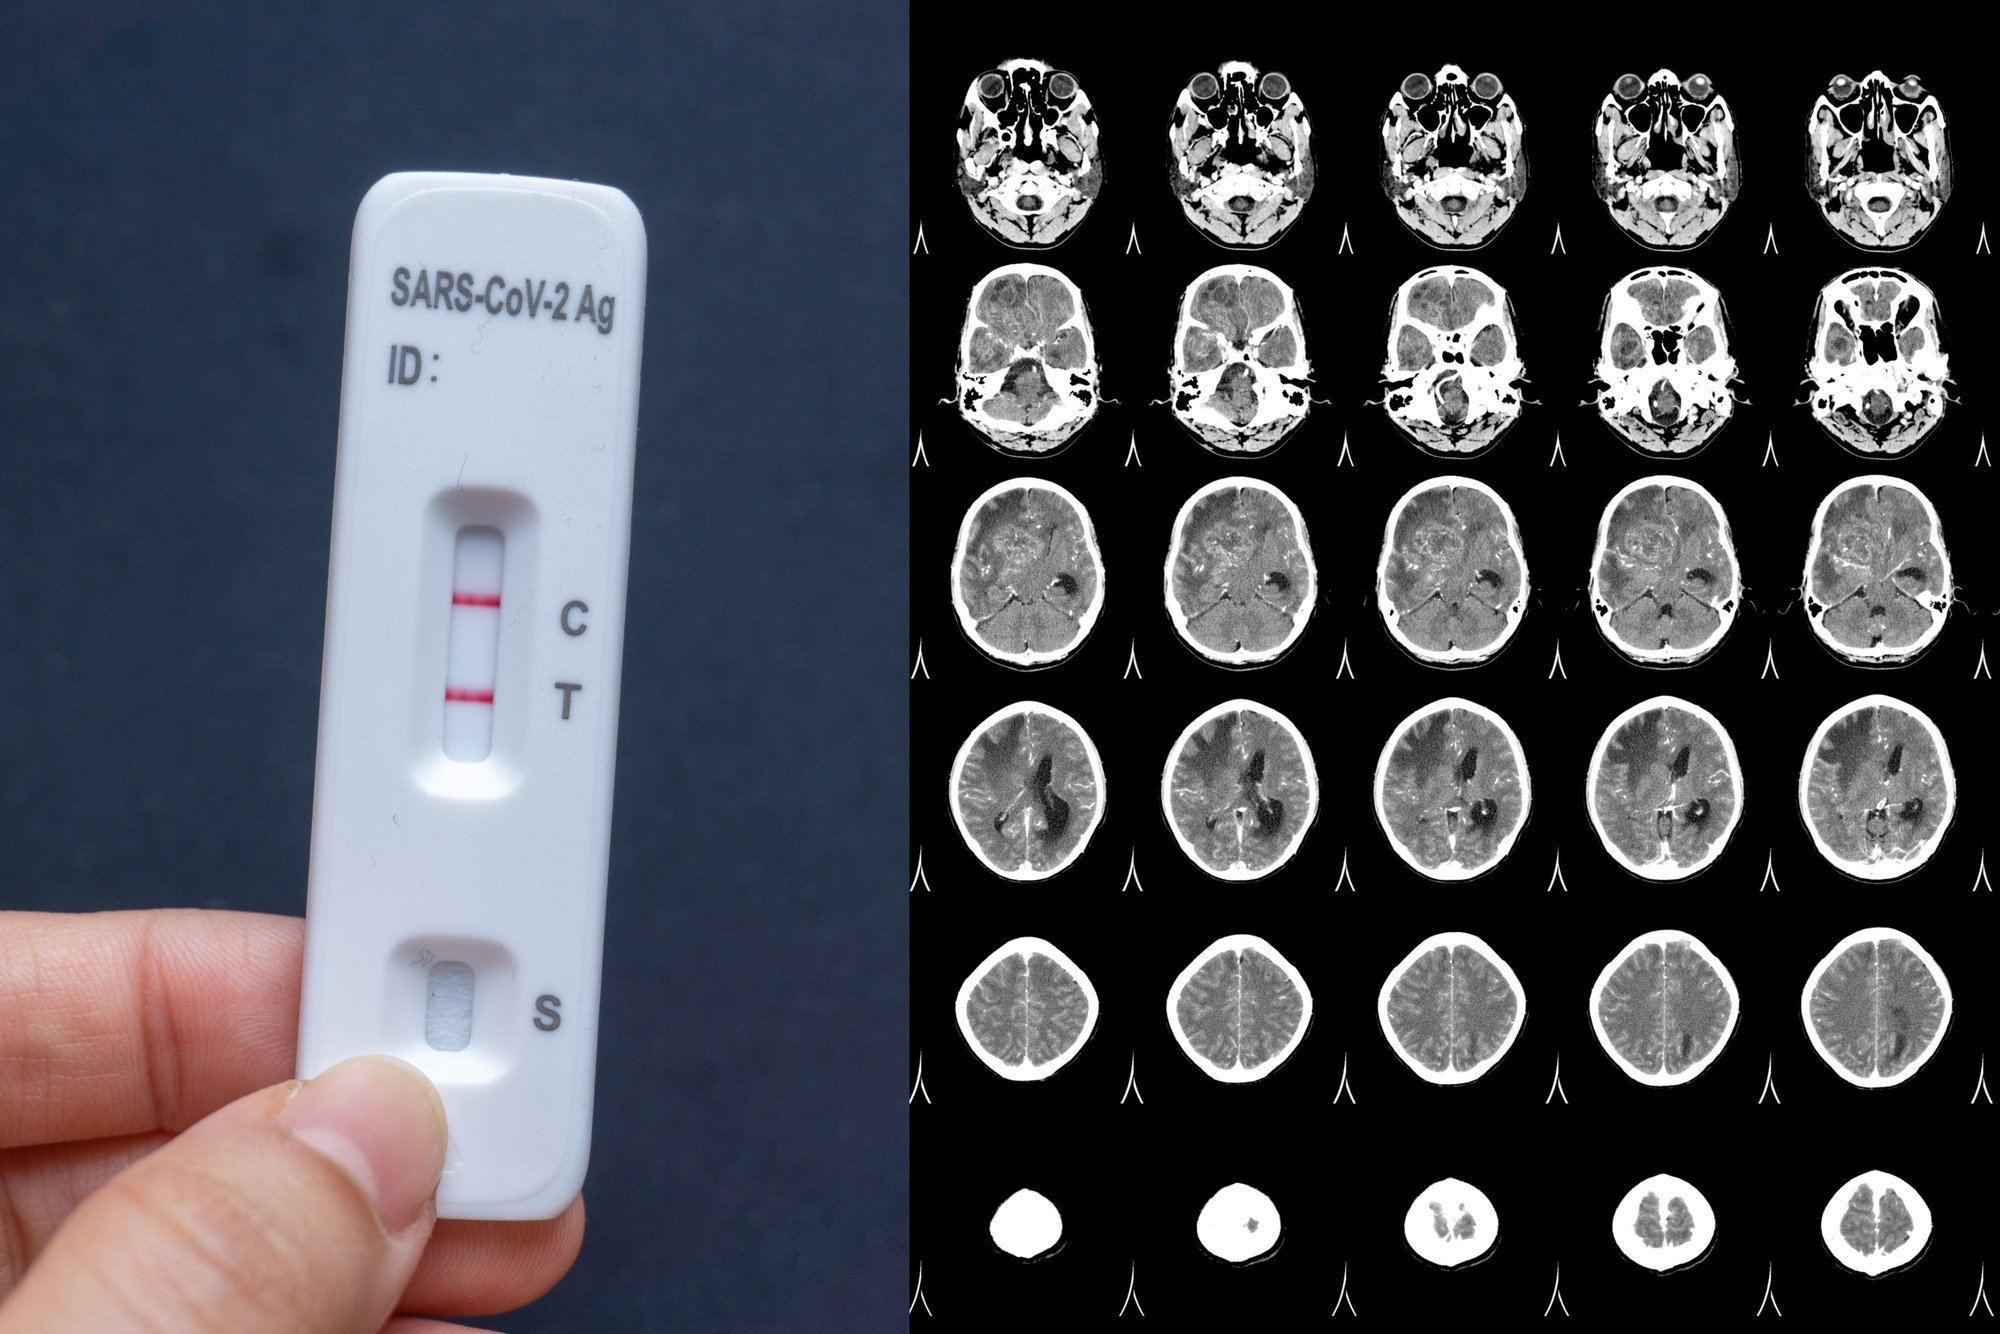

Коронавирус, вызывающий заболевание COVID-19, стал буквально глобальной проблемой. Множество мифов и дезинформации о распространении и последствиях этого вируса появились в социальных сетях и СМИ. Один из распространенных мифов — это утверждение, что мужчины болеют коронавирусом чаще и тяжелее, чем женщины. Но насколько это соответствует действительности?

В конечном итоге, важно понимать, что коронавирус может заразить любого и вызывать тяжелое течение болезни как у мужчин, так и у женщин. Необходимо соблюдать рекомендации по гигиене, ношению масок и социальной дистанции, чтобы защитить себя и других от возможной инфекции.

Коронавирус не выбирает пол и заражает как мужчин, так и женщин. Поэтому, все без исключения, вне зависимости от пола, должны соблюдать основные меры предосторожности: носить маску, периодически мывать руки, избегать скопления людей и соблюдать дистанцию.